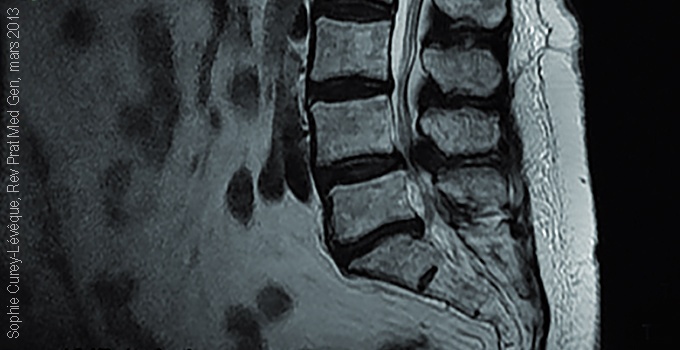

Un examen tomodensitométrique et au mieux une IRM permettent de mesurer le diamètre du canal, de visualiser l’existence de hernies discales, et de mettre en évidence des conflits avec les racines.